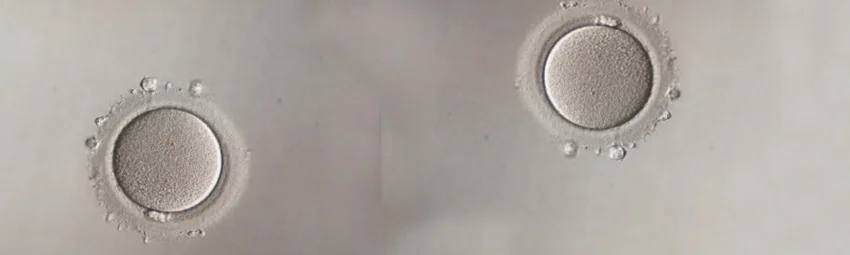

ЭКО с донорской яйцеклеткой — это программа, при которой для оплодотворения используется ооцит донора, а эмбрион затем переносят в матку женщины-реципиента. Такой вариант обычно рассматривают, когда собственные яйцеклетки отсутствуют, их качество или количество резко снижены, есть высокий риск передачи тяжелого генетического заболевания или были повторные безуспешные попытки ЭКО с собственными ооцитами. В программе могут использоваться свежие и замороженные донорские яйцеклетки. При выборе донора ориентируются на анкету, а сам донор проходит обязательное обследование в соответствии с действующими требованиями. Решение о программе принимают только после обследования пары и оценки готовности женщины к беременности. Если в программе используется сперма партнера, генетическая связь у ребенка будет с отцом.

Для лечения бесплодия могут применяться самые разнообразные методы, среди которых самым эффективным является экстракорпоральное оплодотворение (ЭКО). В этом случае процесс оплодотворения происходит вне женского организма, после предварительного получения половых клеток партнеров. Если же по разным причинам получить женские яйцеклетки не удается, то может быть использован донорский материал. В сложных случаях бесплодия именно ЭКО с донорской яйцеклеткой зачастую становится последней надеждой на наступление долгожданной беременности.